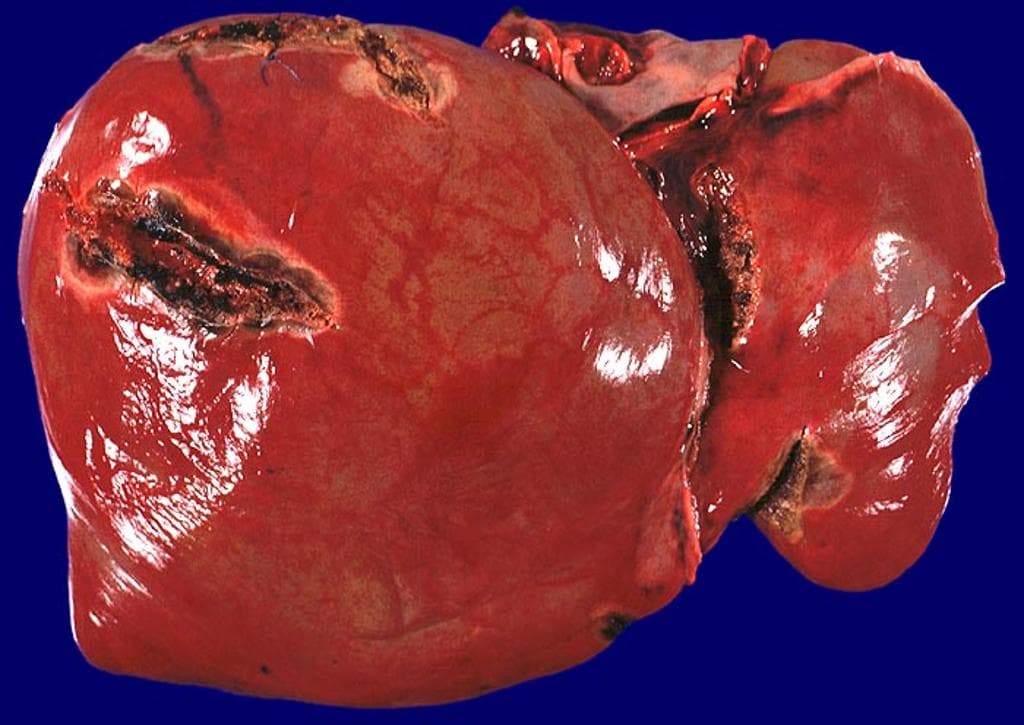

Vết rách gan do chèn dụng cụ nội soi ổ bụng (liver laceration from laparoscopic port insertion)

Traumatic Liver Laceration (Gross Pathology) (Vết rách gan do chấn thương (giải phẫu bệnh đại thể))

- 1.Khối máu tụ dưới màng gan

- 2.Nhồi máu gan do tổn thương mạch máu